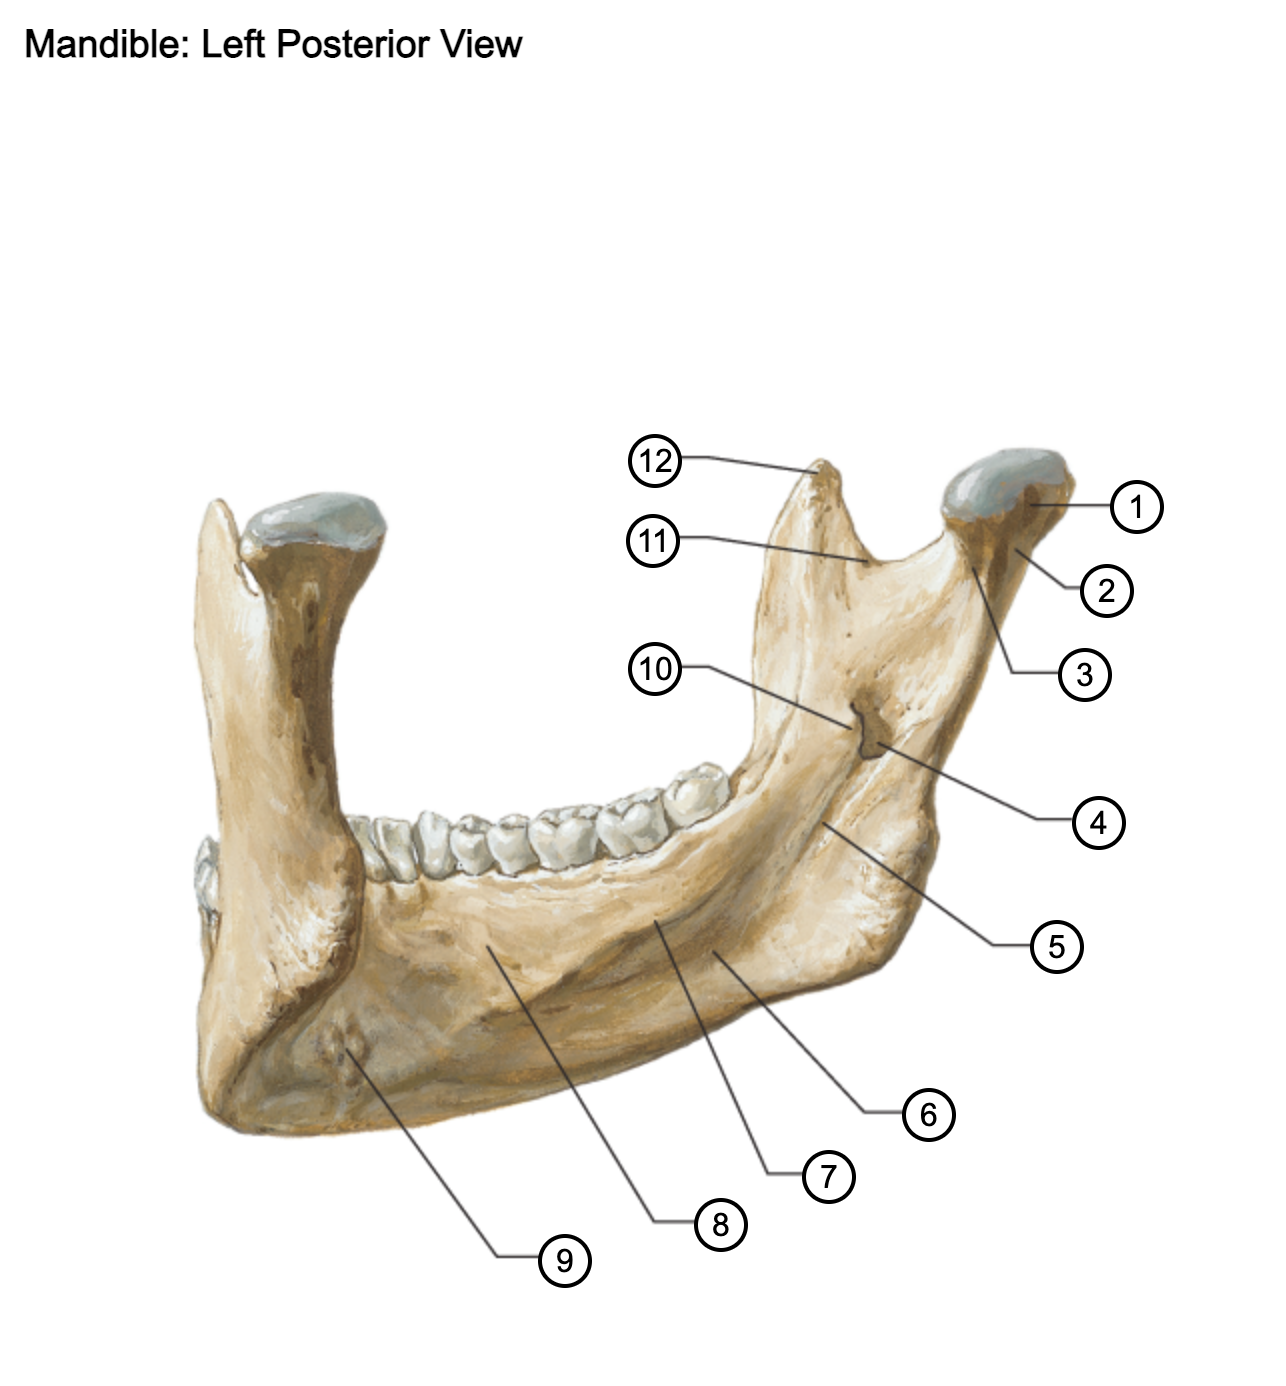

1

condylar process

2

neck of mandible

3

pterygoid fovea

4

mandibular foramen (inferior alveolar foramen)

5

mylohyoid groove

6

submandibular fossa

7

mylohyoid line

8

sublingual fossa

9

superior and inferior mental spines

10

lingula